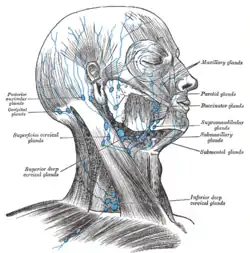

Lymphatic vessels of the head and neck, with the supraclavicular lymph nodes described as "deep cervical lymph nodes", visible at the bottom | |